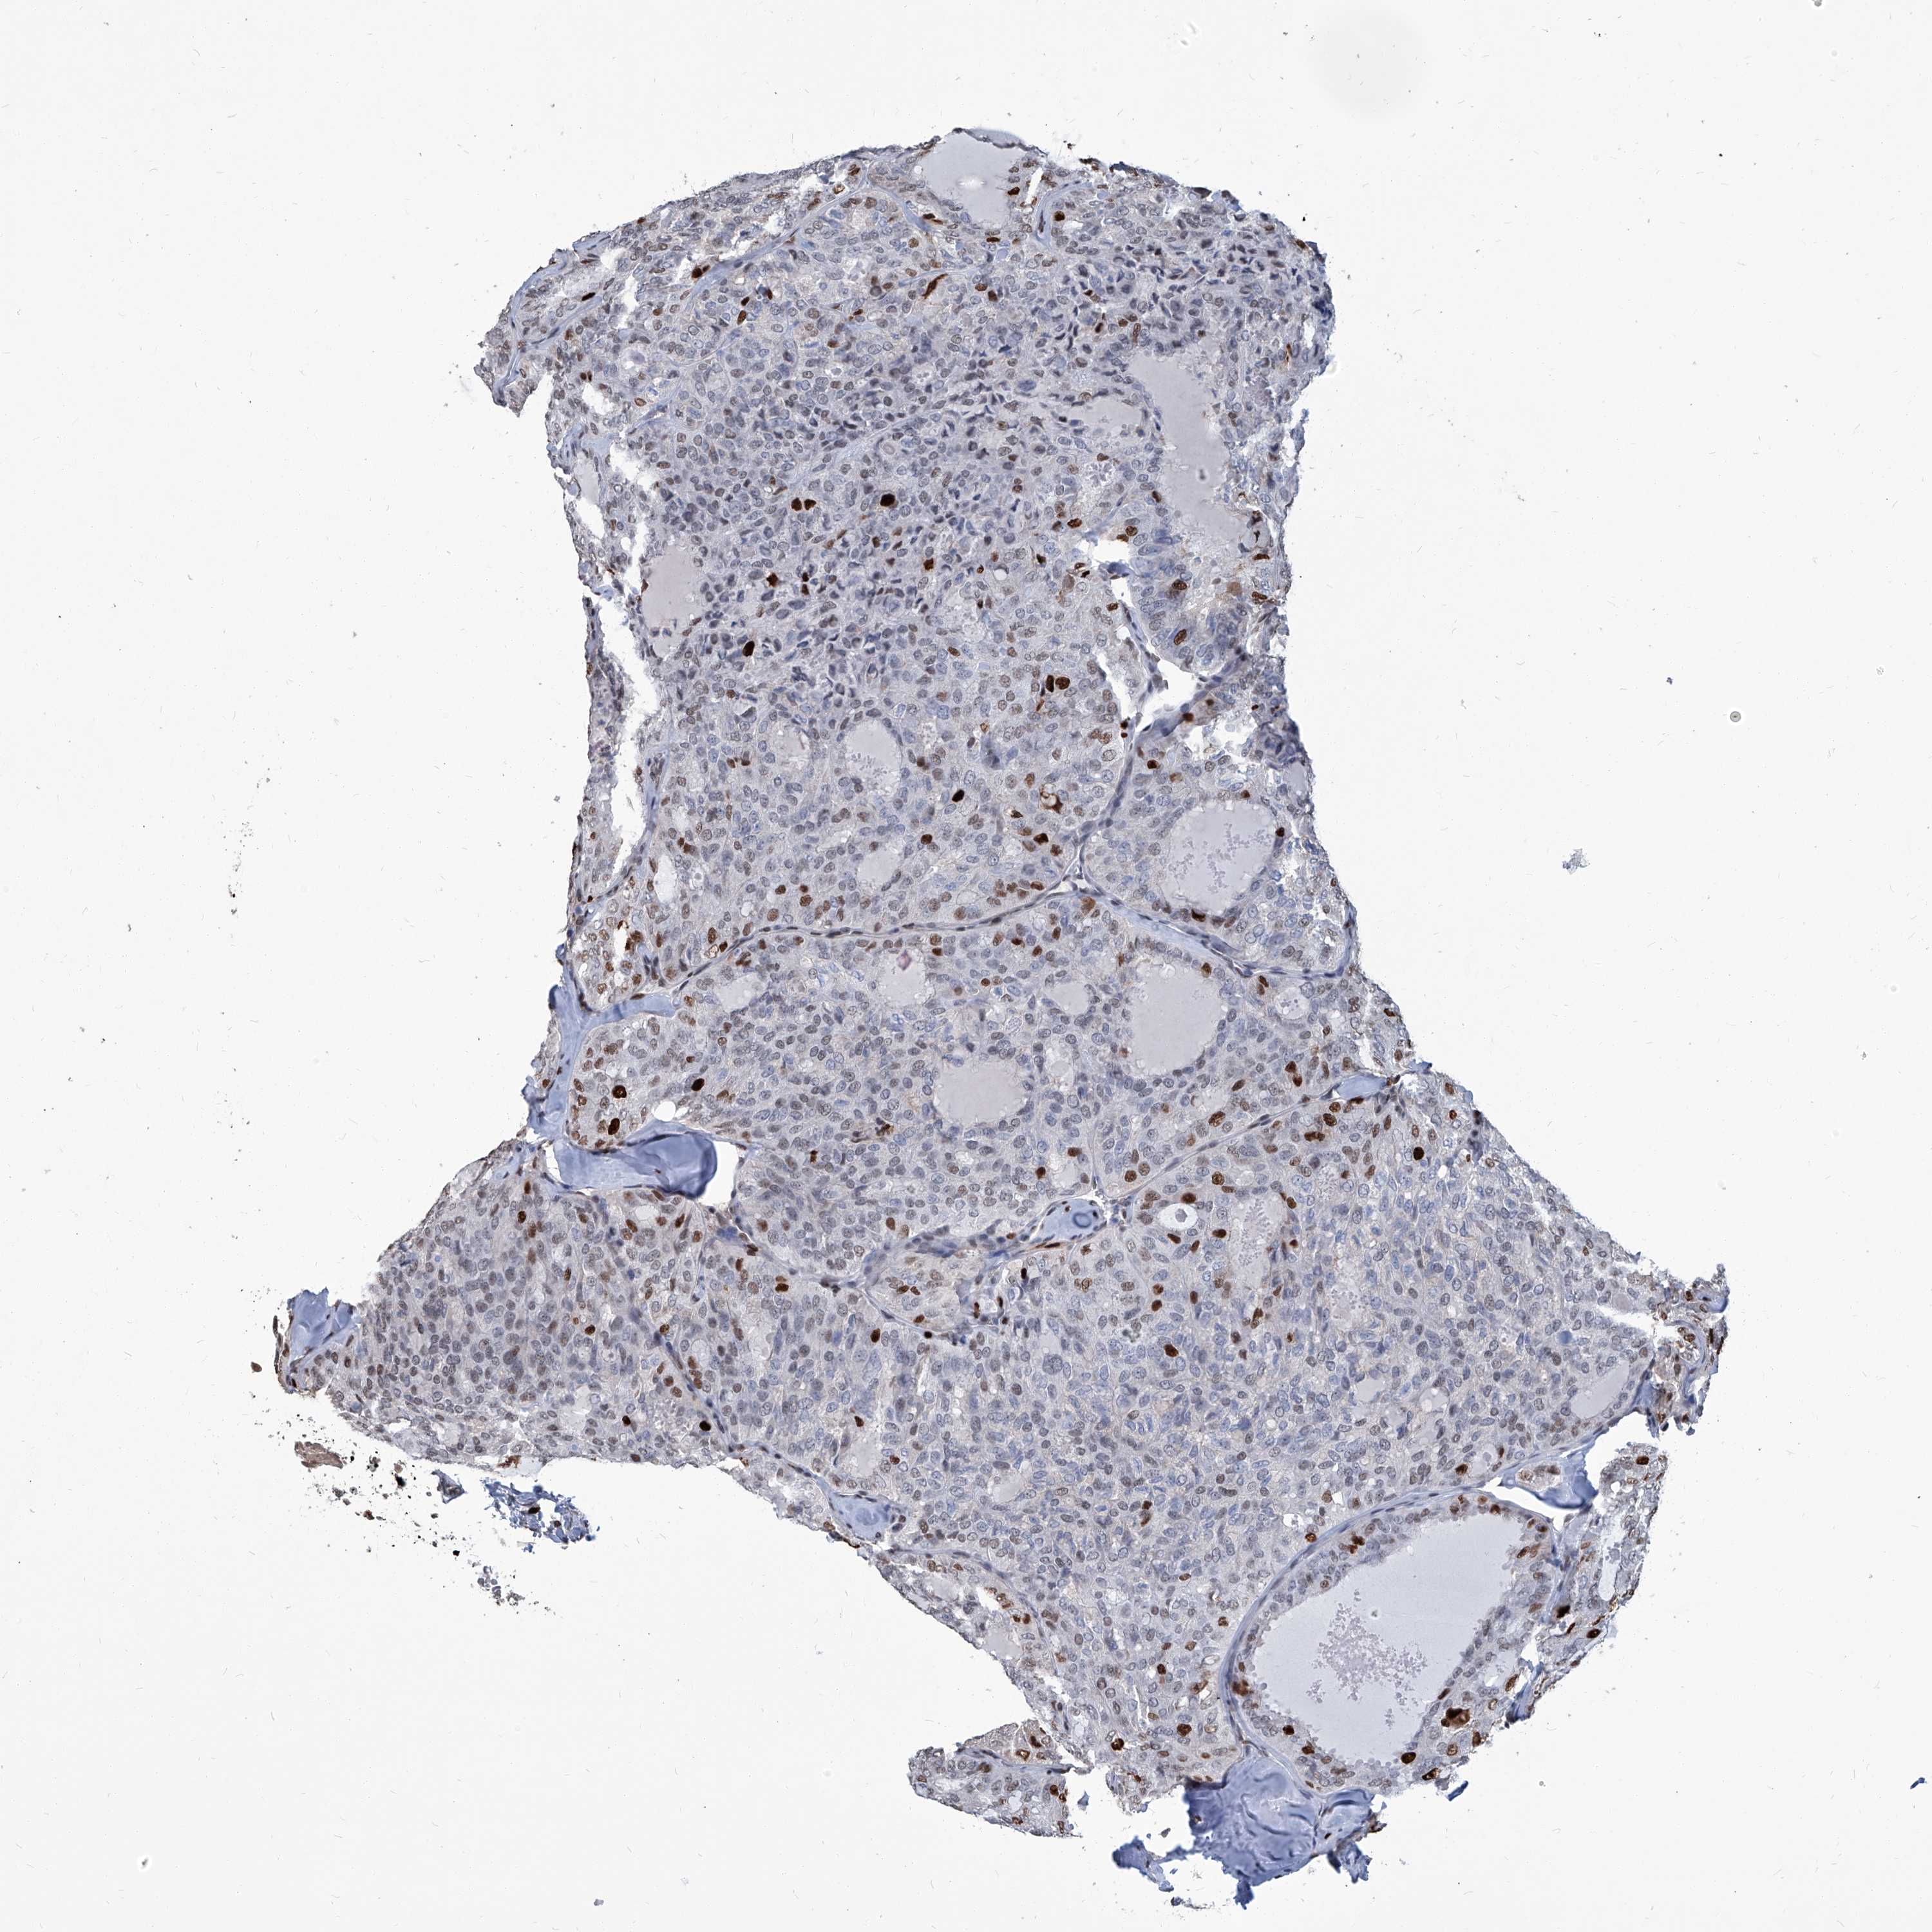

THYROID CANCER - Protein expressioni

A mouse-over function shows sample information and annotation data. Click on an image to view it in a full screen mode. Samples can be filtered based on level of antibody staining by selecting one or several of the following categories: high, medium, low and not detected. The assay and annotation is described here.

Note that samples used for immunohistochemistry by the Human Protein Atlas do not correspond to samples in the TCGA dataset.

Antibody stainingi

Antibody staining in the annotated cell types in the current human tissue is reported as not detected, low, medium, or high, based on conventional immunohistochemistry profiling in selected tissues. This score is based on the combination of the staining intensity and fraction of stained cells.

Each image is clickable and will lead to virtual microscopy that enables deeper exploration of all samples and also displays staining intensity scores, fraction scores and subcellular localization as well as patient and tissue information for each sample.

Staining

High

Medium

Low

Not detected

Intensity

Strong

Moderate

Weak

Negative

Quantity

>75%

75%-25%

<25%

None

Location

Nuclear

Cytoplasmic/membranous

Cytoplasmic/membranous,nuclear

Papillary adenocarcinoma, NOS

Follicular adenoma carcinoma, NOS

Carcinoma, NOS